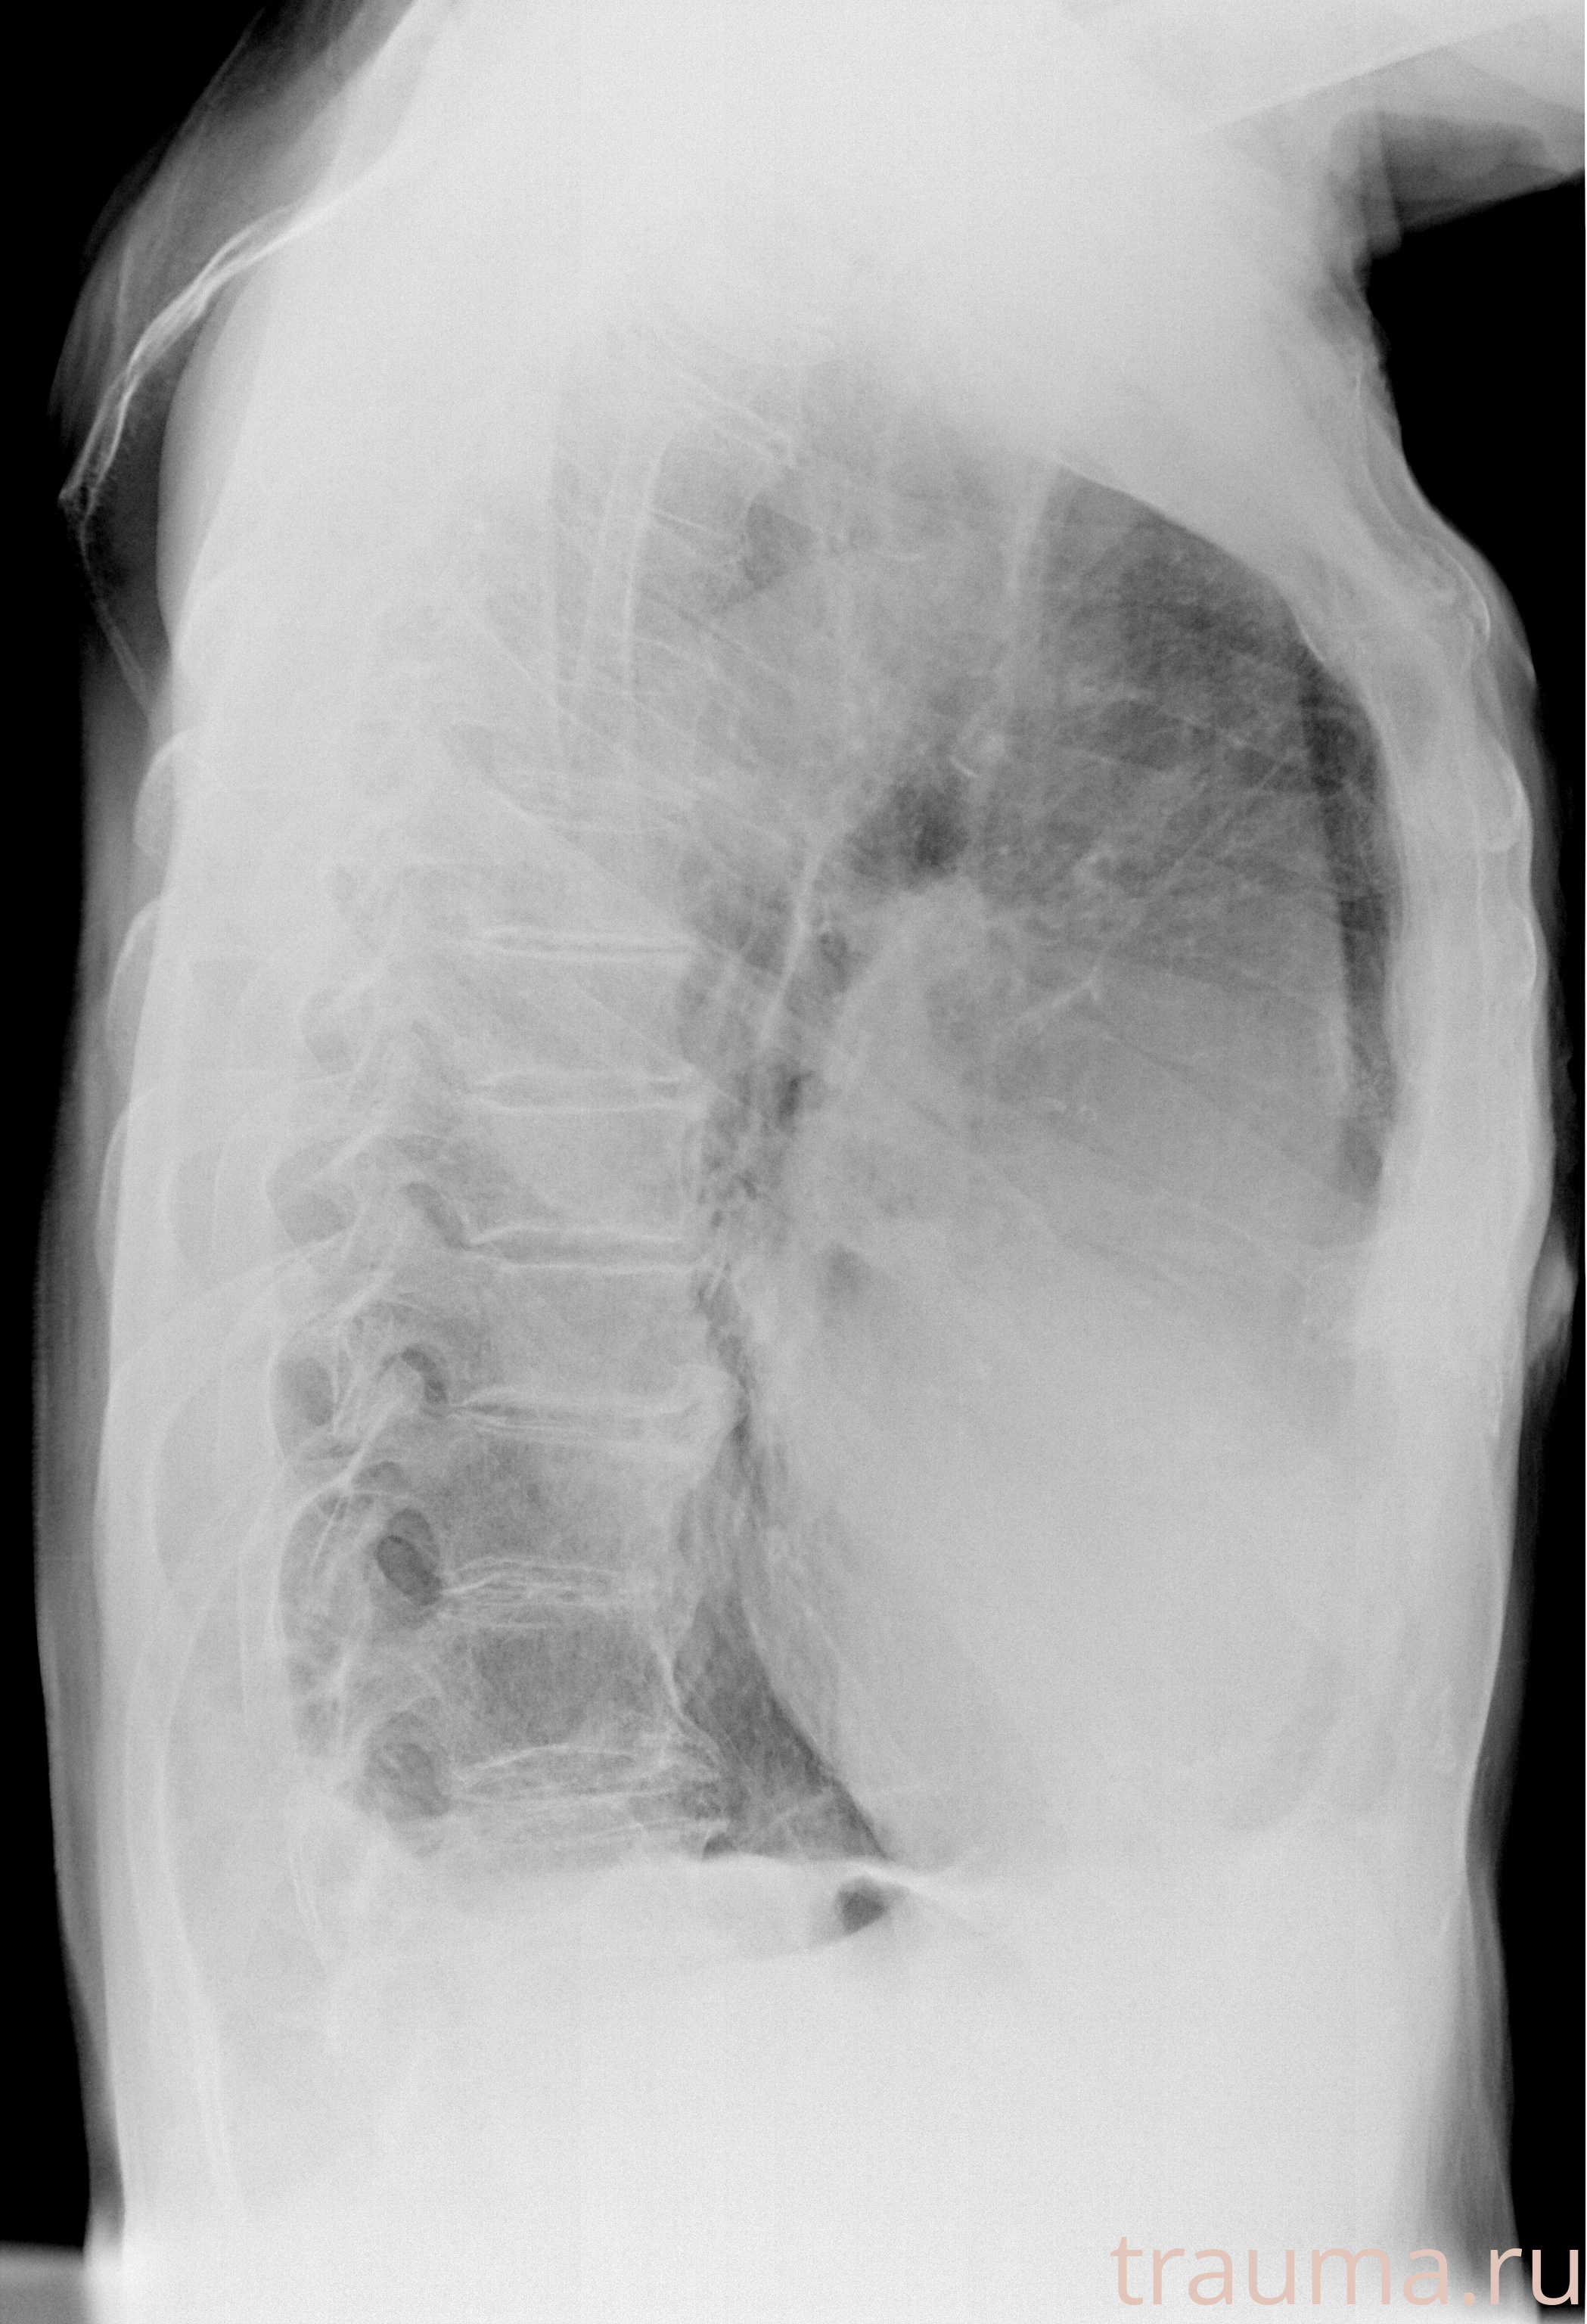

Рентген на дому: по вашему адресу приезжает врач-рентгенолог, травматолог-ортопед с мобильным рентгеновским аппаратом, проводит диагностику травмы или заболевания, делает необходимые рентгенограммы, дает рекомендации по дальнейшему лечению. Получить качественные снимки в домашних условиях возможно благодаря уникальной методике, разработанной МосРентген Центром для института  Склифосовского

при переломе шейки бедра и пневмонии от компании МосРентген Центр - партнера Института имени Склифосовского